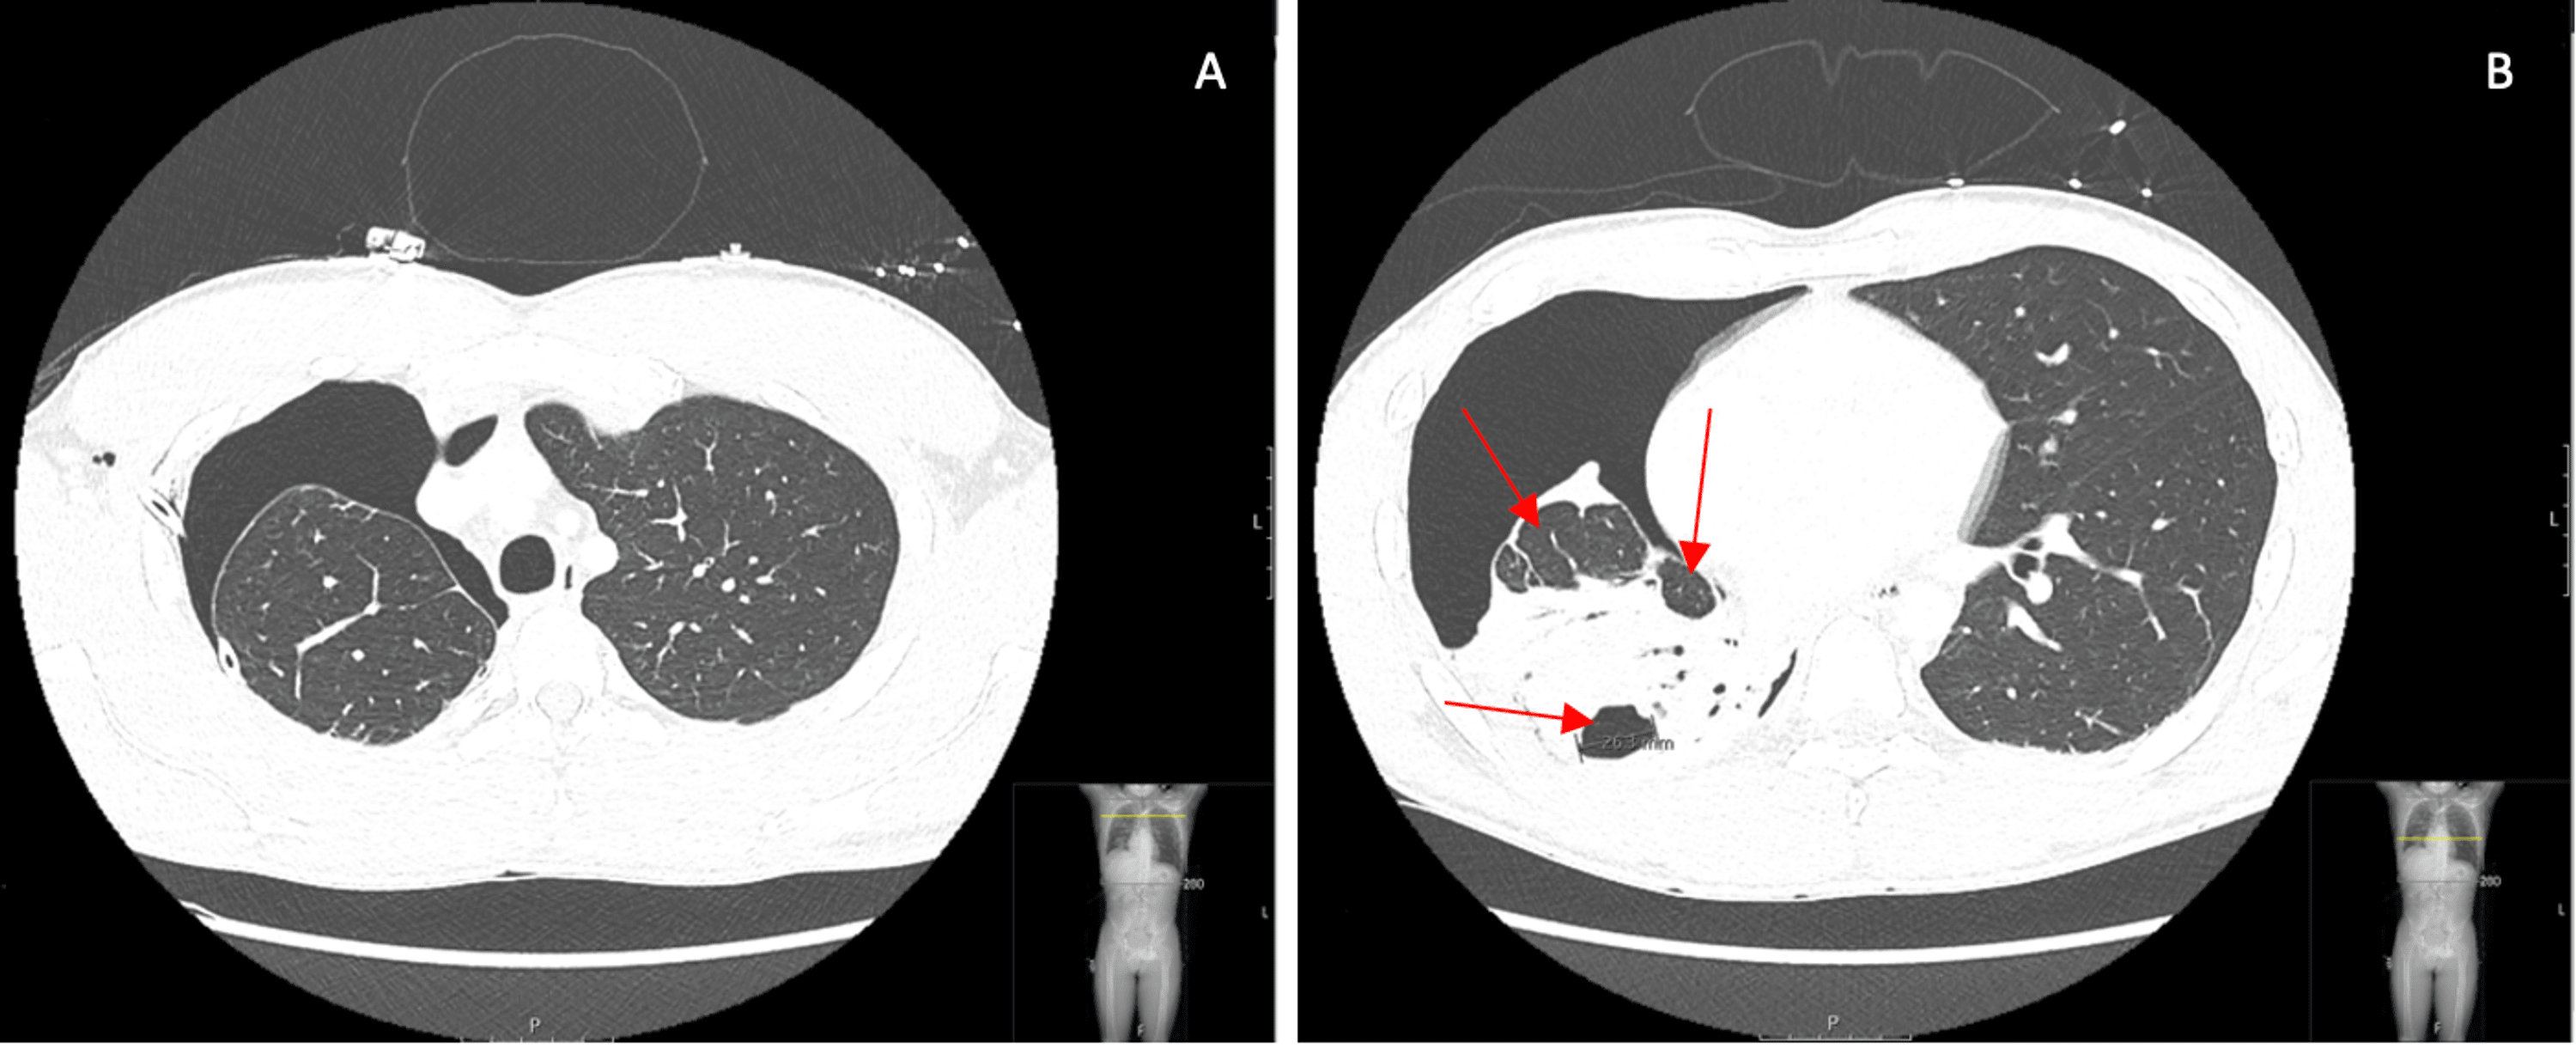

(A) Contrastenhanced CT of the chest at the time of presentation Difference Between Chest Ct With And Without Contrast The most common type of ct scan with contrast is the double contrast study that will require you to drink a contrast media before your exam begins in addition to the iv contrast. The us preventive services task force currently. Almost always, cts should be ordered with or without contrast, not both. Ct without contrast for screening the diagnostic algorithm. Difference Between Chest Ct With And Without Contrast.